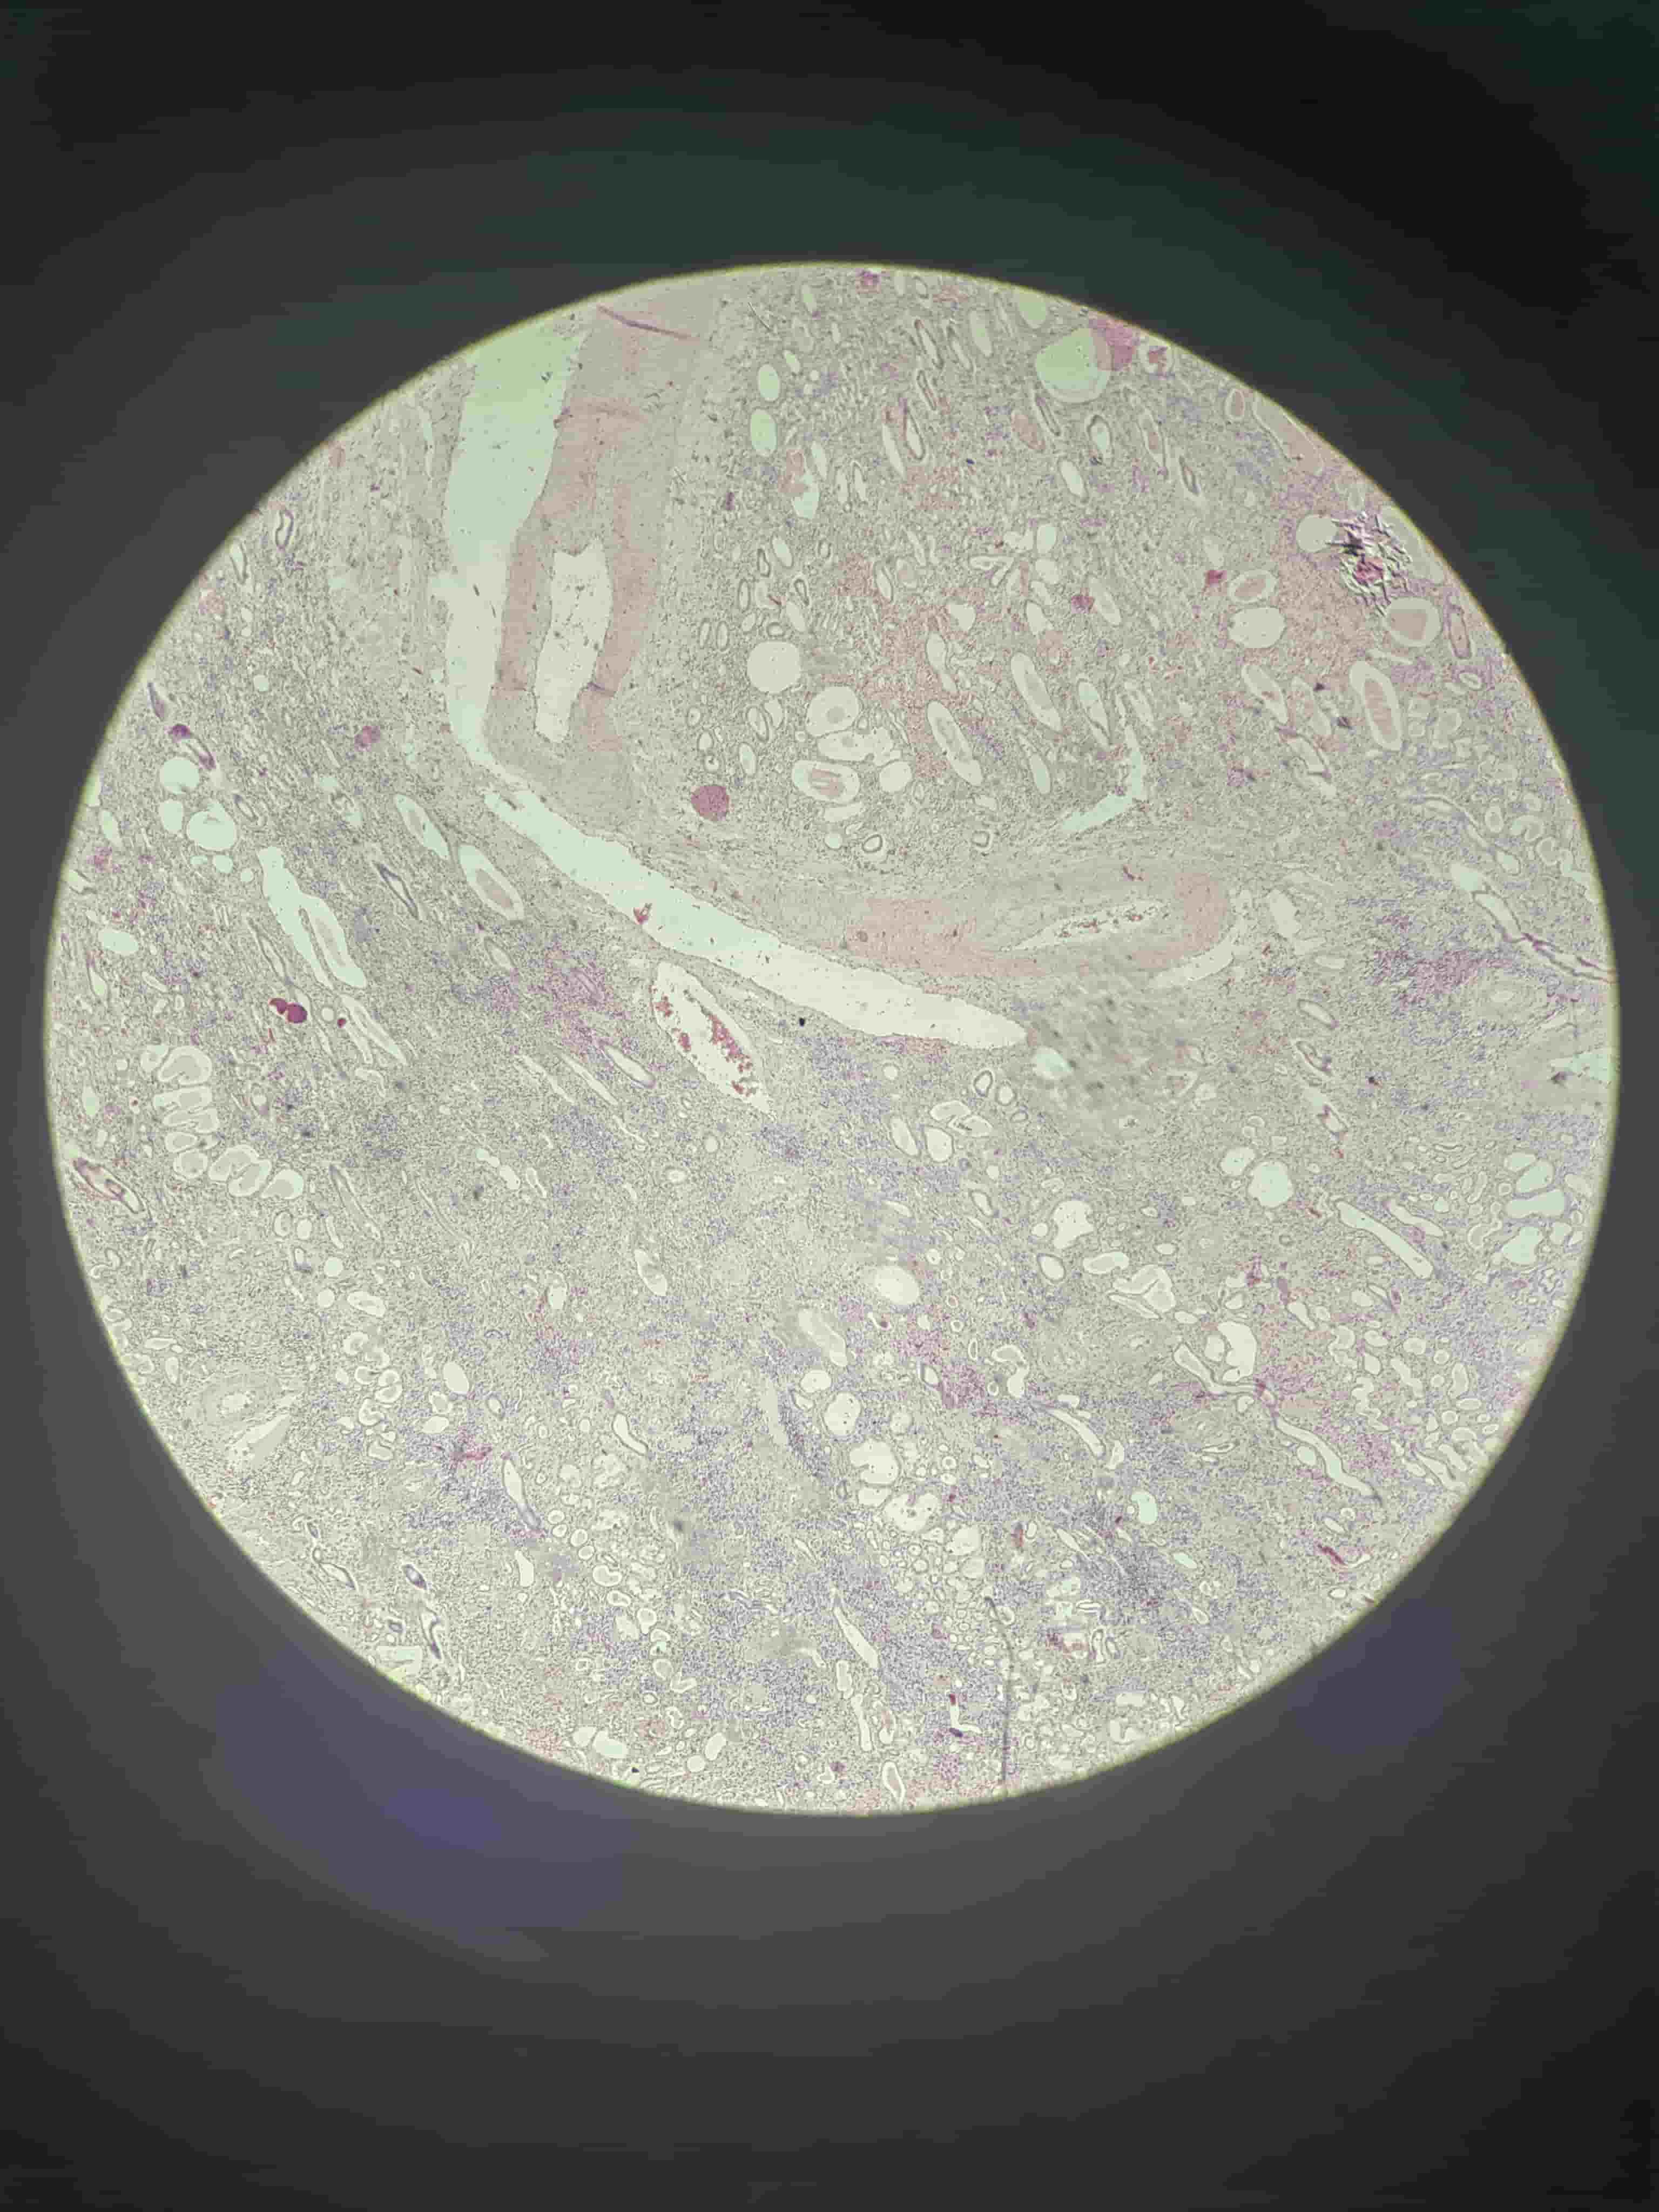

肝细胞脂肪变性

- 石蜡切片含大小不等空泡,为脂滴(被有机溶剂溶解)

- 脂滴推挤使核偏向一侧